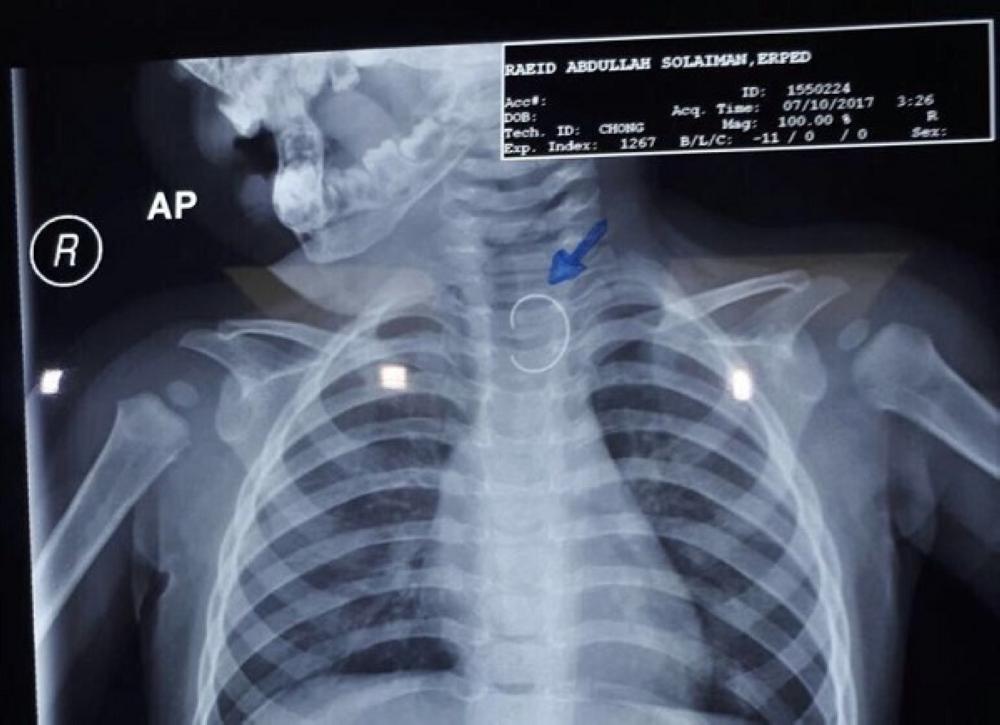

وفي التفاصيل أنه تمت إحالة الطفل إلى أحد المستشفيات بالمنطقة، وبالمعاينة وبعد إجراء فحوصات الأشعة أظهرت النتائج وجود جسم غريب بالمريء عبارة عن (سلك معدني حاد الطرفين)، الأمر الذي تطلب إيضاح الحالة الطبية لولي الأمر وما قد يصاحبها من مضاعفات متوقعة، وضرورة إجراء منظار لاستخراجه، ووافق والد الطفل على الإجراء الطبي وبفضل من الله تم استخراج الجسم الغريب بالمنظار بأمان والحالة العامة للطفل مستقرة.